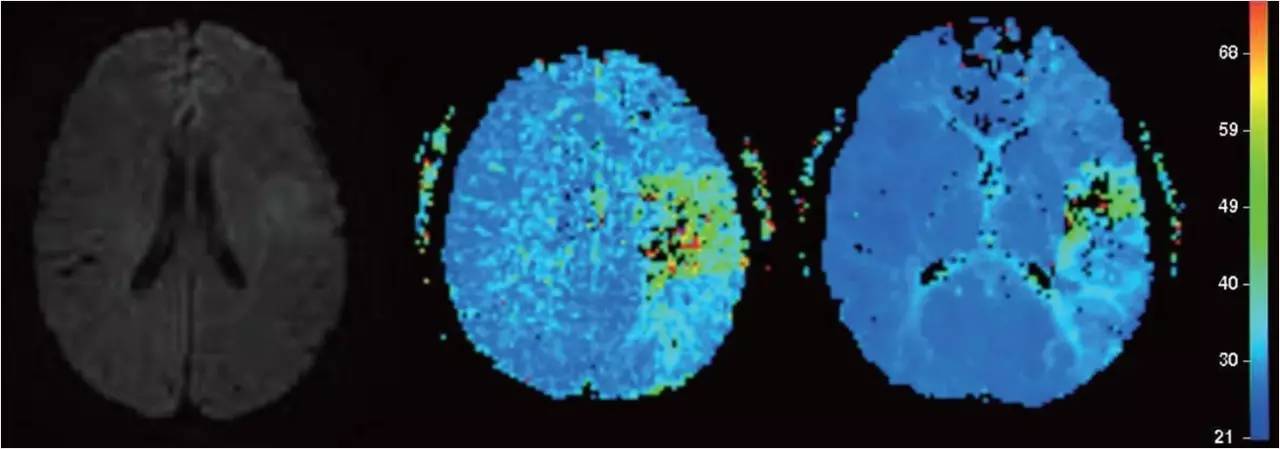

》右侧腹股沟区局部浸润麻醉,常规造影,发现闭塞责任血管后,将微导丝及微导管在导引导管辅助下置于闭塞血管近心端,经微导管注射rt-PA 10-30mg,10min后造影观察血管再通情况 。

》若无再通,微导丝缓慢推进通过闭塞血管,微导管跟进,造影观察闭塞血管远端血管情况,若远端血管通畅,选用取栓支架(Solitaire-AB;ev3 公司,美国)。

》采用NIHSS评分评估术前及术后24h神经功能障碍恢复状况 。

》3月后采用改良Rankin量表门诊或电话评估患者预后。